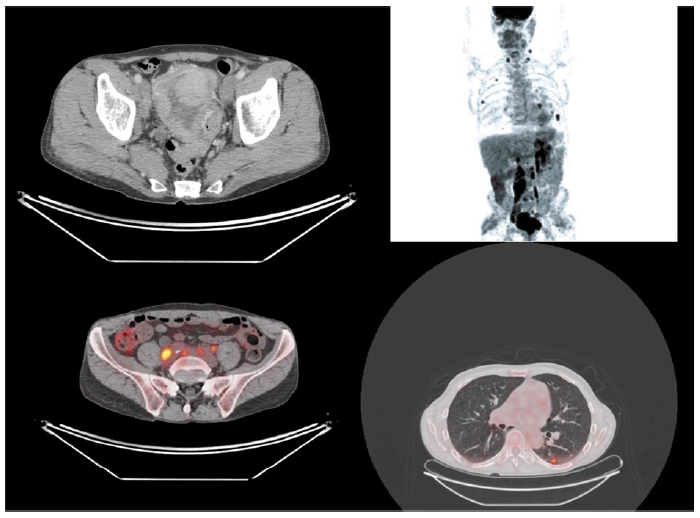

Методы исследования РМП

Существует множество методов визуализации для оценки наличия и распространенности РМП. «Золотым стандартом» визуальной диагностики РМП является цистоскопия [13]. Данный метод применяется для оценки слизистой оболочки мочевого пузыря (МП), устьев мочеточников и уретры. Также одним из относительно недорогих и часто используемых методов визуализации МП без лучевой нагрузки является ультразвуковое исследование (УЗИ) [14]. Для определения локализации и уровня инвазии опухолевого процесса могут применяться как компьютерная томография (КТ), так и магнитно-резонансная томография (МРТ), однако методом выбора считается МРТ [15]. Для оценки опухолевого процесса можно также использовать гибридные методы визуализации, к примеру, позитронно-эмиссионная томография (ПЭТ), совмещенная с КТ (ПЭТ-КТ), и количественная МРТ (диффузионно-взвешенные изображения – ДВИ и карты измеряемого коэффициента диффузии – ИКД) применяются для определения уровня биологической активности и используются в основном для определения стадии и динамики процесса во время лечения (рис. 1) [16–18]. В табл. 1, 2 представлены основные преимущества и недостатки различных методов визуализации образований МП.

Рис. 1. IV стадия РМП с наличием распространения за пределы МП и вовлечением во вторичный процесс запирательных, общих подвздошных, нижних брыжеечных лимфатических узлов и метастатическим поражением легких.

Fig. 1. Stage 4 bladder cancer with invasion and metastasis in obturator, common iliac, inferior mesenteric lymph nodes, and lungs.